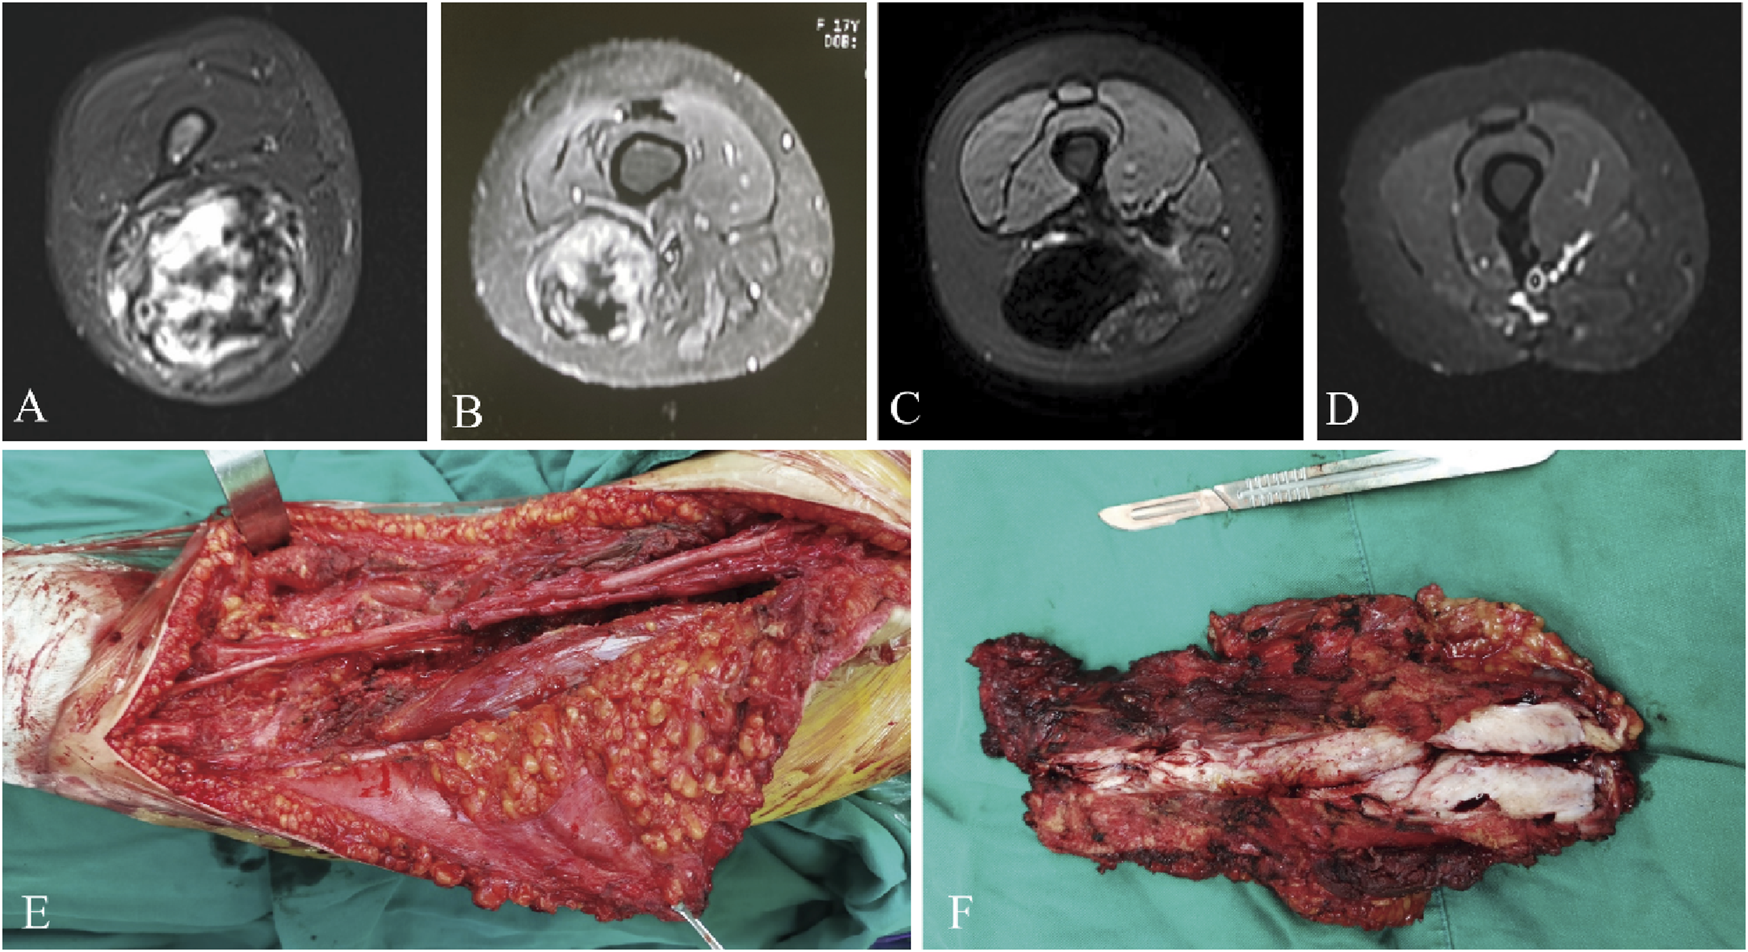

The median RFS was 31 months and the 3-year RFS rate was 37.7% in the surgery alone cohort; the median RFS was 42 months and the 3-year RFS rate was 72.6% in the surgery plus anlotinib cohort. Significant difference in RFS was observed between the two cohorts (p = 0.022, Figure 2). The typical case of the surgery alone cohort was shown in Figure 3: A 20-year-old female patient with postoperative recurrence of DF in the right thigh was included in the surgery alone cohort. The patient still recurred 17 months after surgery with clinical symptoms. The patient was transferred to the surgery plus anlotinib cohort for continued treatment. After preoperative use of anlotinib, the tumor was resected again, the vascular nerve was preserved, and MRI showed no recurrence 14 months after surgery. A typical case of surgery plus anlotinib cohort was shown in Figure 4: A 21-year-old female was diagnosed with DF of the right buttock. The patient visited our hospital for the first time and underwent a needle biopsy at our hospital to confirm the diagnosis. The tumor was resected after preoperative use of anlotinib. MRI showed no tumor recurrence at 27, 39 and 49 months after the operation.

FIGURE 3

A 20-year-old female presented with postoperative recurrence of DF of right thigh (A), which still recurred 17 months after tumor resection in our hospital (B). MRI was re-examined after using anlotinib (C), and the tumor was resected again with preserved vascular and nerve during the operation (E, F), and MRI was re-performed 14 months after surgery (D). MRI, magnetic resonance imaging.

Resection margins of the tumor are less important than maintaining function for the patient and do not have a significant impact on local recurrence (Wirth et al., 2018; Dürr et al., 2020). Unless the tumor was adjacent to the neurovascular bundle, the surgical procedure should aim for extensive resection. For cases with severe complications due to adjacent critical structures or after extensive resection, marginal resection was selected (as shown in Figures 3, 4). In a retrospective study of 426 patients diagnosed with DF, surgical margins (R2 v R0/R1) were found to have a significant impact on progression-free survival (PFS), but R0 v R1 did not (Salas et al., 2011). All surgical patients included in our study achieved R0 or R1 resection, and marginal resection of tumors adjacent to vascular nerves could be regarded as R1 resection, and those who could not reach R1 resection were considered unresectable lesions. Therefore, we did not include surgical margin classification as a study object in this study. Because the patients were compared between two different periods, although tumor resection was performed by the same surgeon in both cohorts, the surgical technique improved over time, which may also be one of the reasons for the decrease in local recurrence rate.